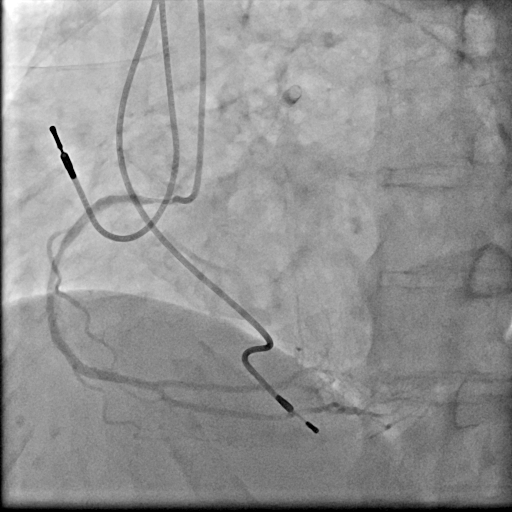

We used 7Fr JR3.5SH guiding and SION blue ES wire. Wire was easily crossed, and IVUS showed in-stent restenosis with neointimal hyperplasia and underexpanded stent. Long inflation technique using cutting balloon was performed, and Biolimus-A9 coated stent was deployed for in-stent lesion. Post dilation using NC balloon was performed, and procedure was completed. 4 months and 1year and 9 months after the procedure, follow up CAG with coronary angioscopy was performed.

1 year and 2 months after the initial procedure using underexpanded stent for eccentric calcified plaque placed at RCA ostium, in-stent restenosis was occurred. PCI was performed with drug-coated balloon and another 8 months later, re-restenosis was occurred. PCI was performed again with Biolimus-A9 coated stent deployed for in-stent lesion. 4 months, and 1 year and 9 months after the stent implantation, CAG was performed with evaluating coronary angioscopy. At the 4 months later, there was no restenosis and we confirmed beginning of neointima coverage for stent strut. At the 1 year and 9 months later, there was also no restenosis, and we confirmed enough and optimal neointimal coverage as vessel healing after stent implantation. Biolimus-A9 coated stent has early drug release system and polymer-free characteristics. The characteristics of the stent may have contributed to get the early smooth and optimal neointimal coverage, and the prevention of malignant cycle of RCA ostium in-stent restenosis.